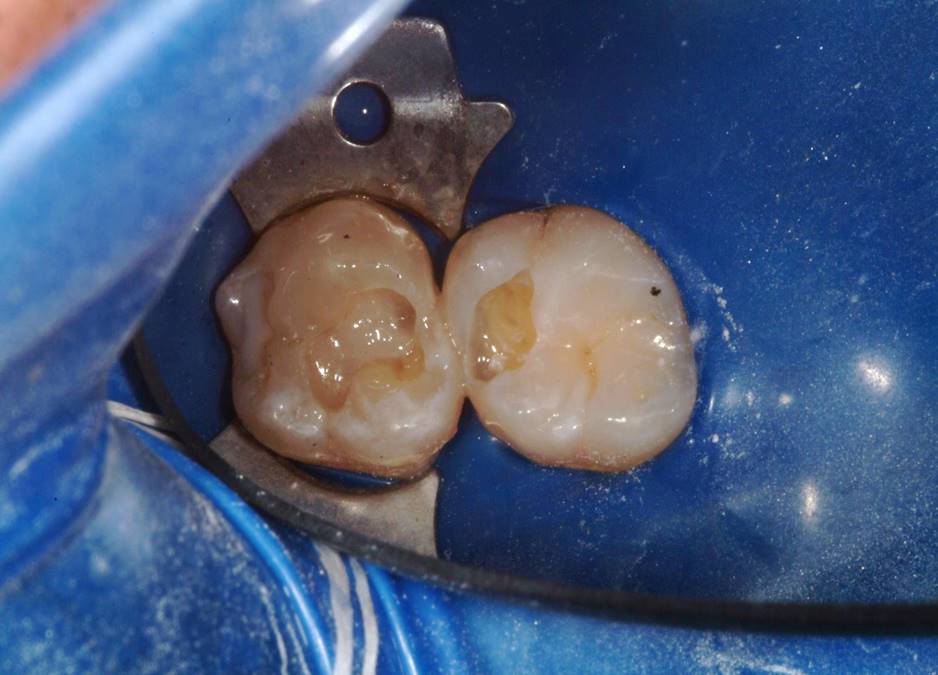

Fig 10. Given the depth of the preparation, the restoration was completed by placing an increment of a nanohybrid composite on top of the flowable bulk-fill dentin replacement.

Figure 10